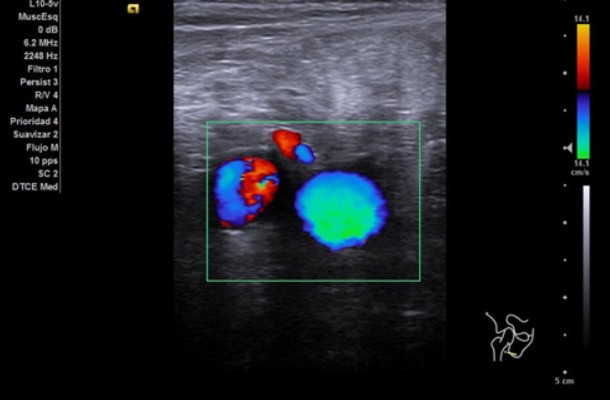

Se realiza ecografía clínica de rodilla derecha y se valora vena femoral derecha desde cayado hasta región poplítea.

A nivel vascular, se exploran ambas venas femorales desde cayado de vena safena hasta la región poplítea con maniobras de compresión mostrando un diámetro conservado, colapsabilidad completa y presencia de flujo a la activación del Doppler color. No se evidencian signos de trombosis venosa profunda.

A nivel articular, se observa líquido articular en zona subcuadricipital en cantidad leve moderada. Resto sin hallazgos relevantes.

La ecografía nos dio la posibilidad de descartar la sospecha de TVP en una paciente con edad avanzada y limitación de la movilidad tras ingreso prolongado. Además, se realizaron controles sucesivos de la artritis sin necesidad de desplazarse al Hospital, teniendo un seguimiento más estrecho, continúo y comparativo respecto a visitas previas. Así, aseguramos una mejor atención y un tratamiento más dirigido. Sin duda, la ecografía nos facilita el trabajo diario y ayuda a manejar la incertidumbre ante patologías potencialmente graves tiempos dependientes.